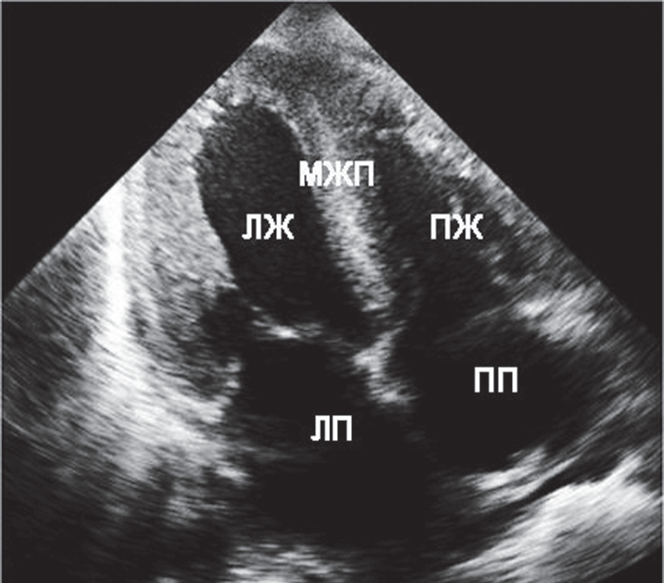

За время пребывания больного в КРО было выполнено исследование крови на Д-димер, уровень которого оказался в результате значительно превышающим норму и составил 3,2 нг/мл. Исследование крови на тропонин показало отрицательный результат. Кроме того, была выполнена ЭхоКГ, продемонстрировавшая значительную легочную гипертензию, гипертрофию левого и правого желудочков, а также снижение фракции выброса до 48 % (рис. 2).

Рис. 2. Эхокадиографическая картина пациента Г. при поступлении в КРО